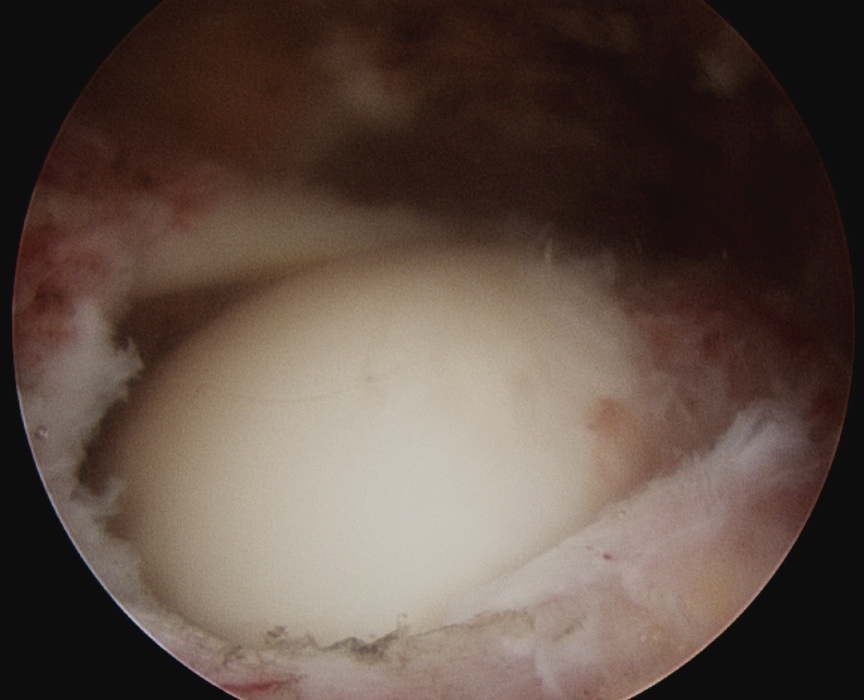

Full thickness tear (FTT)

- variable amount retraction from insertion